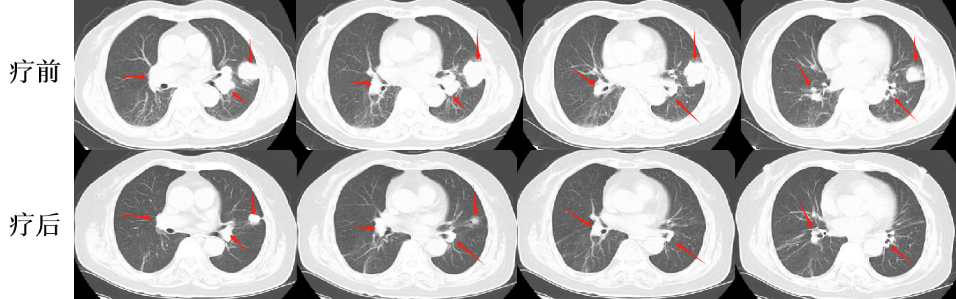

張老太,70歲, 2024年8月因頭暈頭痛,頻繁嘔吐等癥狀入院。頭部磁共振檢查顯示,顱內(nèi)多發(fā)腦轉(zhuǎn)移瘤病灶(見圖)。同時(shí),患者胸部CT檢查可見肺內(nèi)多發(fā)較大腫瘤病灶(見圖)?;颊哂?024年8月20日行CT引導(dǎo)肺腫物穿刺活檢。病理診斷為肺腺癌。綜合診斷為肺腺癌IVB期,腦、肺內(nèi)、右腎上腺多發(fā)轉(zhuǎn)移?;颊哌M(jìn)一步行腫瘤組織基因檢測(cè)和免疫檢查點(diǎn)分子——細(xì)胞程序性死亡配體1(PDL1)檢測(cè)。

圖注:胸部CT檢查,肺內(nèi)多發(fā)較大腫瘤病灶。

患者于2024年08月20開始接受頭部放療。采用最新一代智慧化精準(zhǔn)放療系統(tǒng)——Halcyon“速銳刀”,成功控制患者全部顱內(nèi)病灶,過程順利,沒有明顯副反應(yīng)發(fā)生。患者基因檢測(cè)結(jié)果為陰性,沒有找到具有靶向治療藥物的突變基因。此外,患者年齡較大,體質(zhì)較弱,全身多發(fā)轉(zhuǎn)移病灶,為治療帶來了巨大的挑戰(zhàn)。然而,患者PDL1檢測(cè)顯示,PDL1高表達(dá)(PD-L1 TPS=98%),提示免疫治療有效率較高。潘振宇教授團(tuán)隊(duì)為患者制定了個(gè)體化精準(zhǔn)腫瘤治療方案,僅僅每3周應(yīng)用1次免疫治療藥物。經(jīng)過3次治療后復(fù)查,患者肺內(nèi)病灶顯著縮退,顱內(nèi)病灶縮退。治療過程中,僅出現(xiàn)一過性皮疹。目前患者恢復(fù)良好,生活完全自理。

圖注:治療后復(fù)查胸部CT顯示,肺內(nèi)病灶明顯縮小。